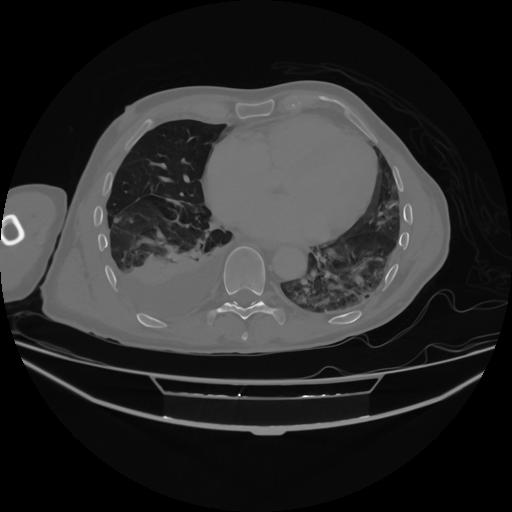

5 CUERPO,CE,Vol,1.0,CUERPO,,